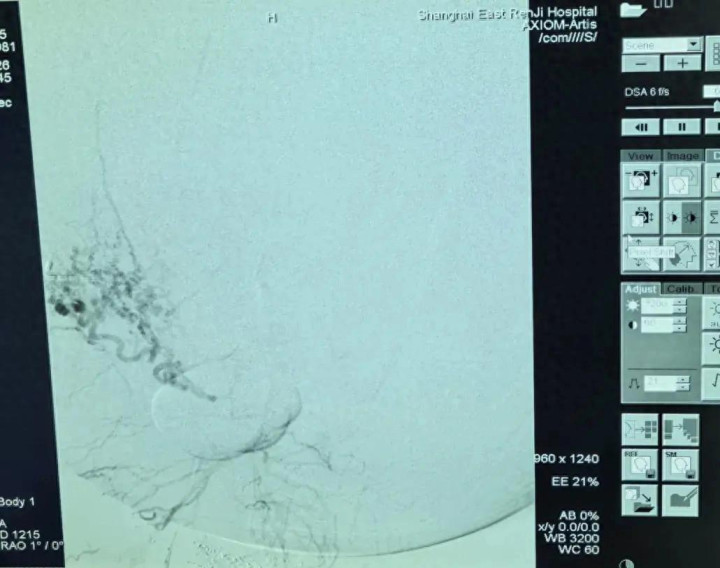

第一棒交给肿瘤介入科主任张学彬。在DSA(数字减影血管造影)的精确调换下,张学彬凭借娴熟的本事,生效找到并栓塞了肿瘤的多支润泽动脉,为后续手术毁灭了最大的“路障”。